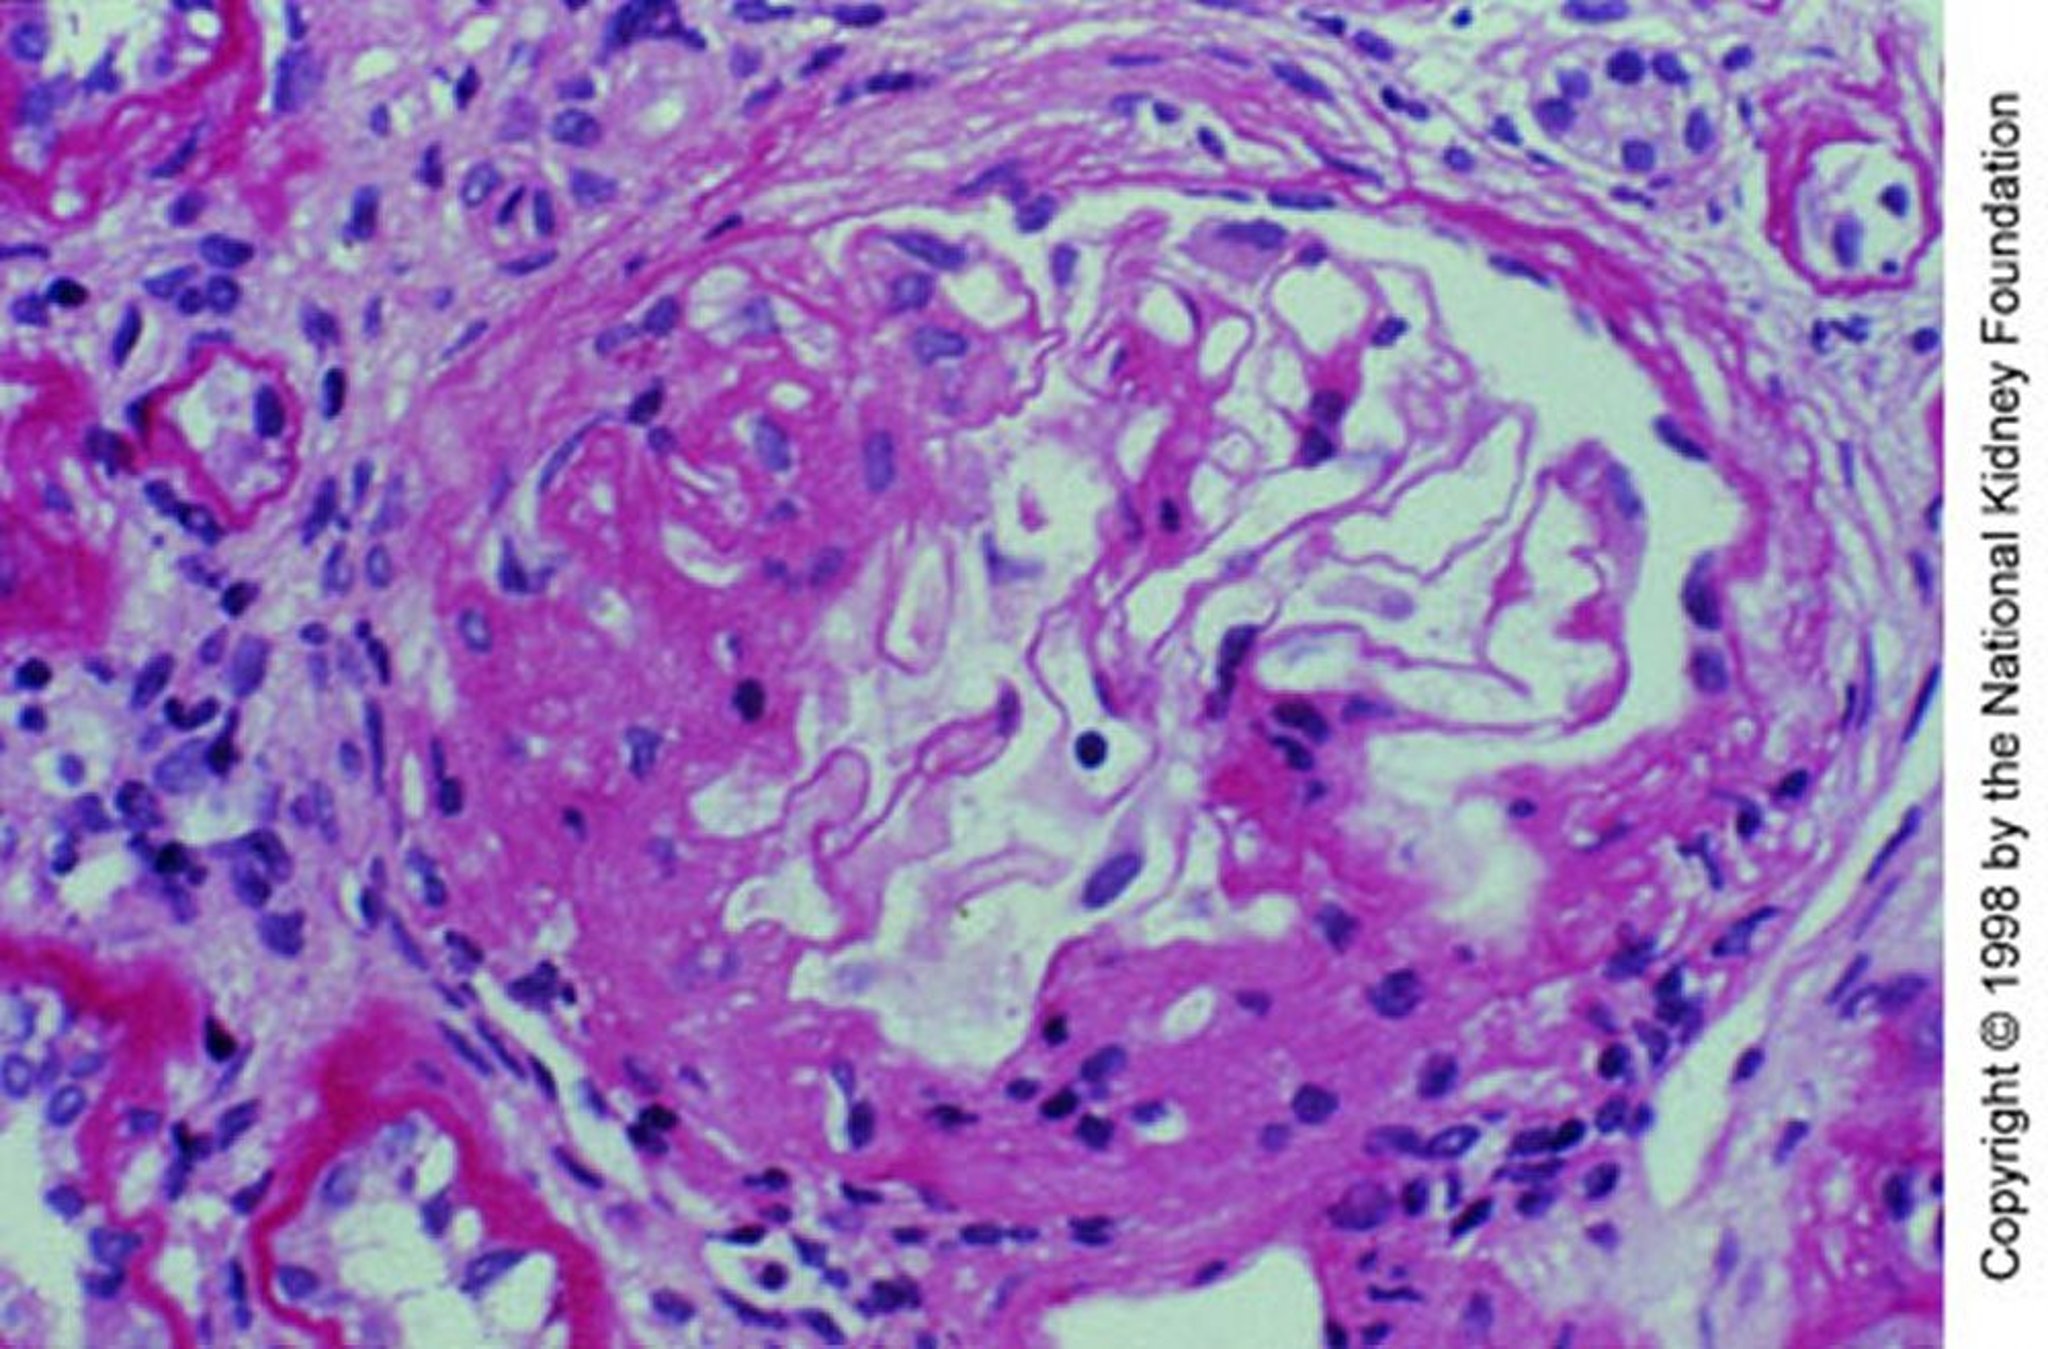

Bệnh thận do IgA (mở rộng gian mạch)

Tăng sinh gian mạch với xơ cứng từng phần (nhuộm axit-Schiff định kỳ, ×200).

Hình ảnh do bác sĩ Agnes Fogo và American Journal of Kidney Diseases' Atlas of Renal Pathology cung cấp (xem www.ajkd.org).